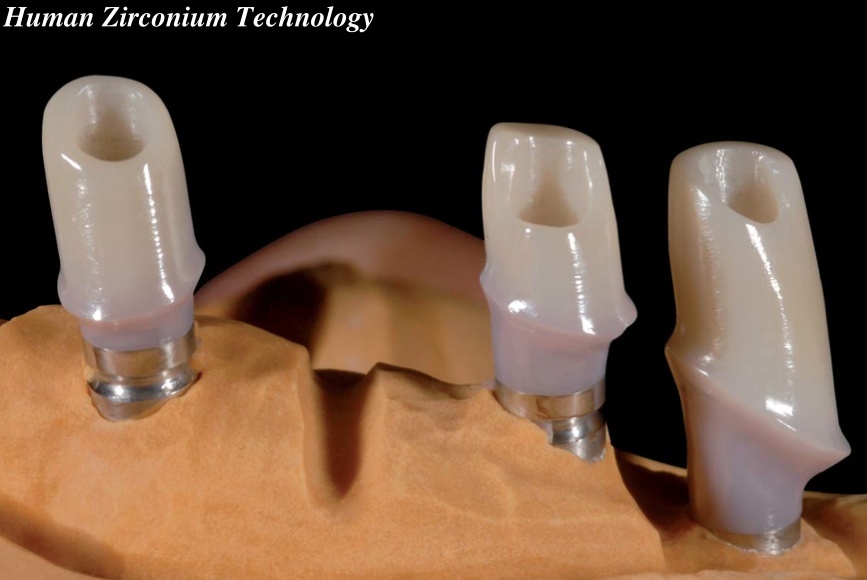

Циркониевые коронки и штифты: современные решения в стоматологии

Раздел: Необычные решения